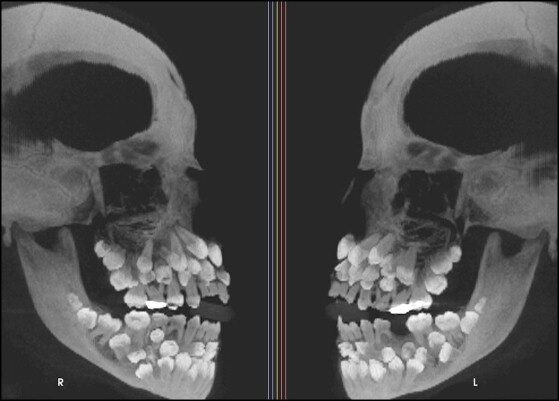

Sự việc bắt đầu khi một bé gái 11 tuổi 8 tháng tuổi đến phòng khám nha khoa ở Minas Gerais, Brazil, với mong muốn nhổ bỏ hàng răng sữa trên cùng vẫn chưa rụng. Tuy nhiên, kết quả chụp X-quang đã hé lộ một sự thật không ngờ: tổng cộng có 18 răng sữa, 32 răng vĩnh viễn và đáng kinh ngạc là 31 chiếc răng thừa ẩn sâu bên trong hàm.

Khi thăm khám ban đầu, các bác sĩ nhận thấy chỉ có 5 răng vĩnh viễn đã mọc, trong khi phần lớn răng sữa vẫn còn nguyên vẹn. Để có cái nhìn toàn diện hơn về tình trạng răng miệng của bệnh nhân, bác sĩ đã chỉ định chụp X-quang tổng quát và chụp sọ nghiêng. Những hình ảnh này không chỉ xác nhận số lượng răng bất thường mà còn cho thấy nhiều răng bị biến dạng và nằm sâu trong nướu, khiến việc phân biệt giữa răng bình thường và răng thừa trở nên vô cùng khó khăn.